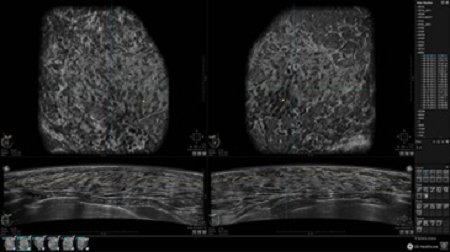

GE INVENIA ABUS – это современный УЗИ аппарат, который создан для точной и эффективной диагностики сканирования с высокой плотностью молочных желез. Выявляемость патологий раковых и предраковых стадий заболевания составляет 55%, что в конечном счете позволяет ставить врачу точные и своевременные диагнозы. Традиционные методы использования маммографии не показывают такой выявляемости, ограничиваясь лишь 3-38%.

УЗИ-аппарат GE INVENIA ABUS позволяет проводить максимально операторонезависимые процедуры, что значительно снижает риск неправильной постановки диагноза и сопутствующие издержки на обработку информации. Система готовит отчет в течение 3-х минут после сканирования, это безусловное преимущество по сравнению с обычным УЗИ сканером.

• Получение объемных 3D изображений с возможностью покадрового просмотра

• Отображение объемных 3D ультразвуковых изображений, которые состоят из традиционных поперечных и воссозданных коронарных и сагиттальных проекций

• Стандартизованная ориентация изображения: «толстый срез» в коронарной плоскости; поперечная; сагиттальная плоскость; радиальный и антирадиальный поворот изображения; просмотр исключительно области интереса